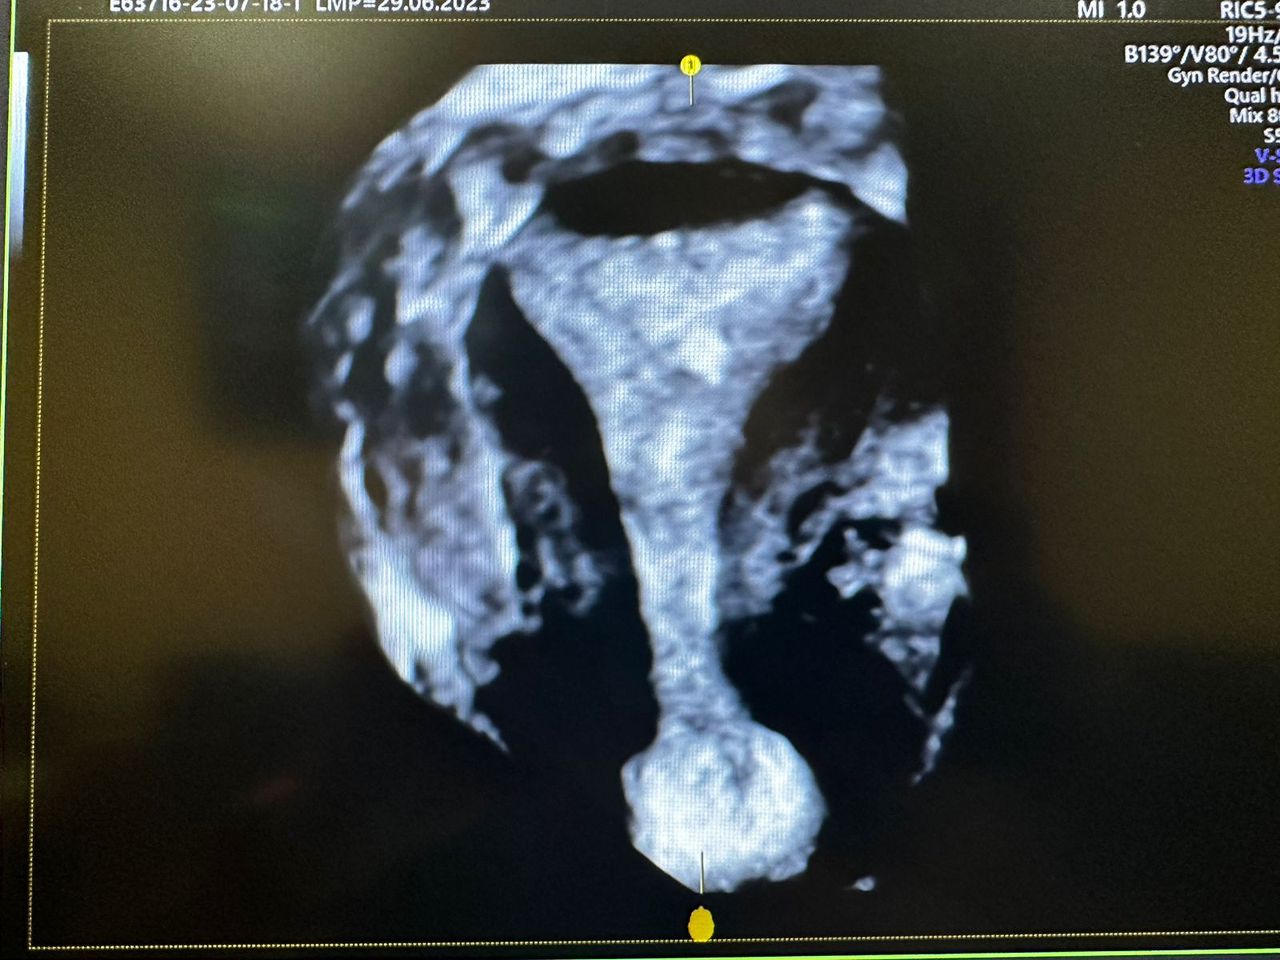

Ultrasonido 4D

Histeroscopia

Fertilización in vitro (FIV)